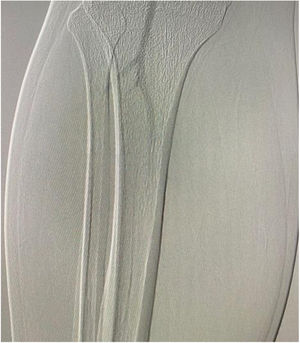

El estudio inicial fue una ecografía doppler arterial de ambos miembros inferiores que mostró ausencia de flujo a nivel infrapatelar bilateral, compatible con vasoespasmo severo u oclusión arterial aguda de vasos distales. Se realizó el examen físico, que mostró frialdad distal, ausencia de pulsos pedios, llenado capilar prolongado (>10segundos), limitación para la extensión y flexión de los artejos, alteración en la sensibilidad plantar y pie caído bilateral (fig. 1). Debido a la sospecha de IAAE, se realizó una arteriografía de miembros inferiores, que confirmó la presencia de vasoespasmo distal en las arterias tibial anterior, tronco tibioperoneo, tibial posterior y peronea, con patrón de pie desierto en ambas extremidades (fig. 2). Cabe resaltar que no se utilizó la tomografía computarizada de vasos como primera opción debido a la ausencia de disponibilidad en el momento.